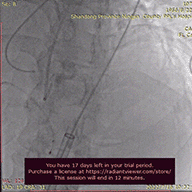

在Ecmo辅助下,行主动脉根部造影,猪尾确定选择最佳释放体位,观察瓣叶活动,确认是否合并反流,选择合适体位跨瓣。

主动脉根部根部造影

术者团队用25mm球囊预扩,结合瓣环及球囊预扩情况,预装AV29型号瓣膜。患者横位心,在抓捕器辅助下输送器过弓。

球囊预扩

造影评估

术者结合DSA影像,多角度观察瓣膜情况,在瓣膜释放至工作位造影。

初始定位释放

工作位

无明显返流,瓣膜形态佳,工作稳定。

工作位评估

完全释放